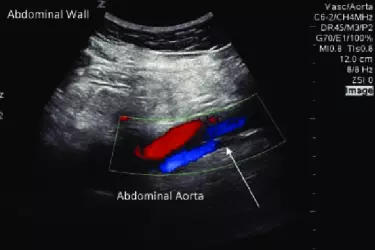

Aorta is the blood vessel which carries the blood pumped by the heart. From the Aorta the blood goes into different arteries. The flow of blood in the aorta is with a lot of high pressure. This can cause weakening of the walls of aorta and result in an aneurysm. Abdominal Aortic Aneurysm (AAA) is a rare condition and mostly asymptomatic. Due to this reason many patients with AAA are missed out and in the event of rupture of the aneurysm, saving the life of the patient becomes very difficult. Most of the cases of AAA are incidental findings during Ultrasound Abdomen Examination and that too if the radiologist is well experienced. If aneurysm is detected on ultrasound, then colour doppler study of abdomen is done to confirm the diagnosis. CT Angiography or MR Angiography can be followed to get more detailed information about the aneurysm before going for surgical repair of the aneurysm.

Apart from the Aorta, there are many more arteries and veins in the abdominal area. Abdominal Colour Doppler is advised when the patient has Swelling / palpable lump in abdomen, enlarged liver or spleen, blood in vomitting or stool, fatty liver, cramping pain the abdomen after meals etc. Studies included under abdominal colour doppler are portal vein colour doppler study, hepatic vein colour doppler study, mesentric colour doppler study. The advantages of colour doppler studies of the abdomen are that it has no radiation and can be performed quite easily even on pregnant women. There is no contrast that needs to be injected and even the patients with poor kidney function can get this test. The cost of colour doppler is also lower than contrast CT Scan or MRI of the abdomen which also makes it an attractive investigation for vascular diseases of the abdominal organs.